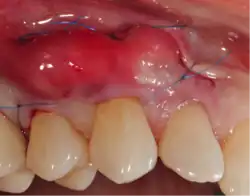

A small amount of blood (10 millilitres (0.35 imp fl oz; 0.34 US fl oz) per tube) is harvested and spun in a centrifuge for eight minutes at 1300 RPM. A fibrin clot packed with blood-derived growth factors, extra cellular matrix and hematopoietic stem cells is fabricated and implanted into the gums above the area of gum recession. Advanced platelet-rich fibrin will promote the patient's own gums to fabricate more gum thus eliminating the need to harvest gums from the roof of the mouth or the use of allografting tissue.

Following this procedure, patients have an improved quality of recovery and require less recovery time due to enhanced healing factors.[15][16][17][18]